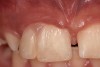

Using the wax-up as a guide, a composite restoration was fabricated for fused teeth Nos. 7 and 8 by roughening the affected area without pulpal exposure, etching the enamel, and applying primer and adhesive. Composite shade A1 was bonded to the mesial and distal surfaces, with gingival dark composite applied to the cervical “interproximal” region. The tooth was then carved to resemble two teeth, matching the width of the created tooth central to tooth No. 9 (Figure 4 and Figure 5). The patient and her family were very pleased with the result, and no postoperative sensitivity was reported.

Fig 4 and Fig 5. The fused tooth was carved to resemble two teeth, matching the width of the created tooth central to tooth No. 9.